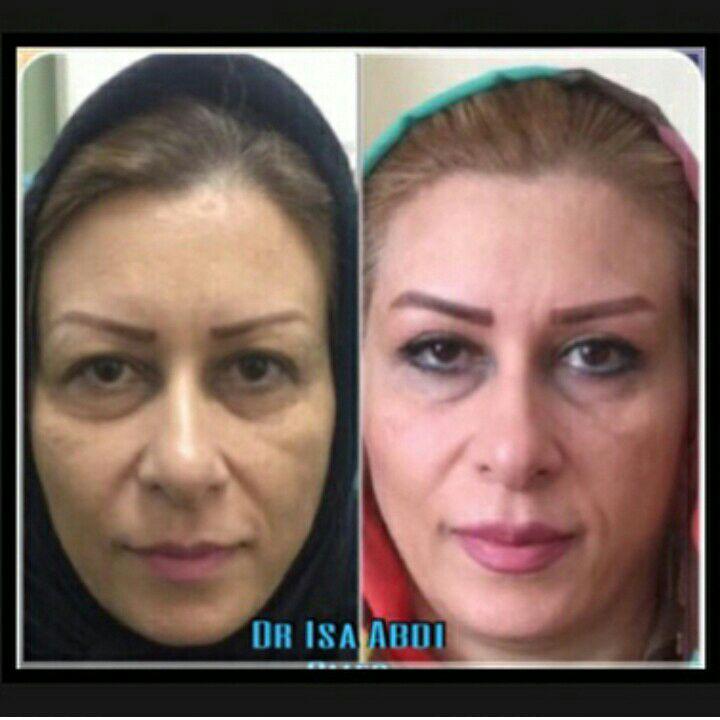

دکتر عیسی عبدی در رشت

دکتر عیسی عبدی در رشت

– متخصص جراحی فک , پلاستیک صورت و بینی

دکتر عیسی عبدی در رشت

تزریق ژل و بوتاکس